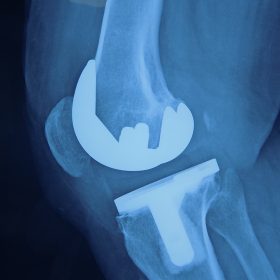

Σε αυτό το σημείο η Αρθροπλαστική Γονάτου αποτελεί μονόδρομο.